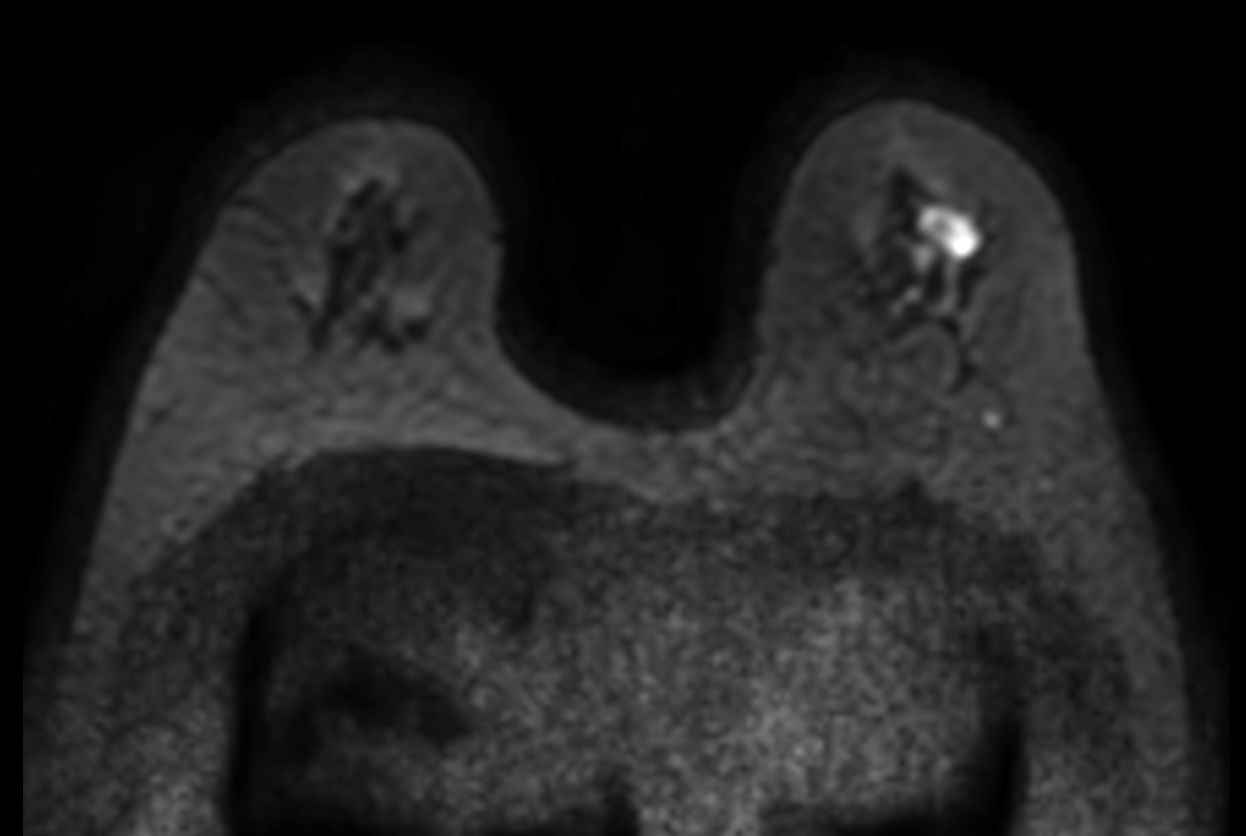

Diffusion (b750)

-